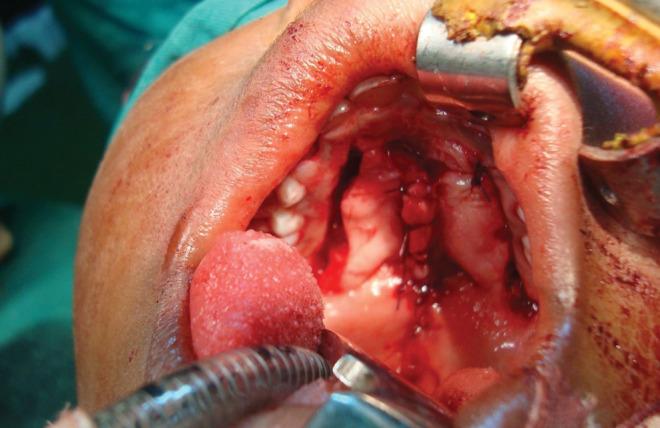

Congenital palatal fistula or perforation is rare, unlike the acquired form which commonly results from cleft palate repair. Congenital palatal fistulae are often associated with submucous cleft palate. Only a few of this fistulae are diagnosed shortly after birth. We present the case of a 3-year old girl with congenital palatal fistula coexisting with cleft of the soft palate that was noticed shortly after birth. The palate was repaired using Bardach's palatoplasty and the client was subsequently referred to a speech therapist.

先天性腭瘘或穿孔很少见,与后天性形式不同,后者通常由腭裂修复引起。先天性腭瘘常与黏膜下腭裂相关。只有少数此类瘘管在出生后不久被诊断出来。我们报告一例3岁女孩的病例,其先天性腭瘘与软腭裂并存,出生后不久就被发现。采用巴尔达克腭成形术修复腭部,随后该患者被转诊至言语治疗师处。